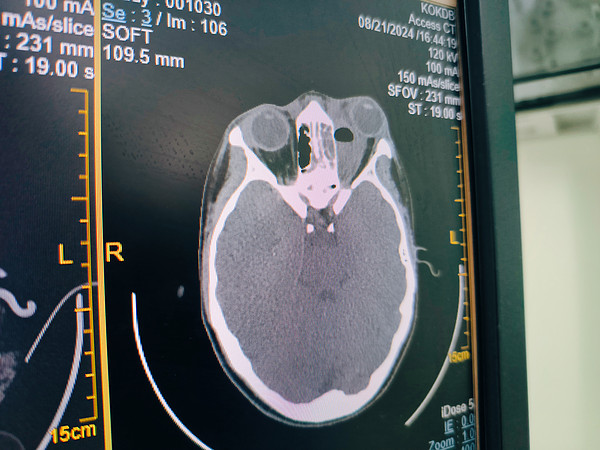

Команда кировских врачей спасла глаз и зрение шестнадцатилетней пациентке